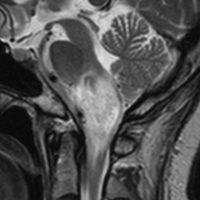

延髄のもの:びまん性正中グリオーマと組織鑑別する必要があるか?

30代の患者さんです。起立性低血圧や呼吸苦,右片麻痺と多彩な脳神経症状で発症しました。

左はT2強調画像で,延髄を中心とするびまん性グリオーマの所見です。右はがドリニウム増強像で,一部が増強されて白く見えています。

50.6Gy/28fr, TMZ 24コースの治療をした4年後のMRIです。腫瘍は縮小して固まったようにみえ,症状も落ち着いて自宅で暮らせてました。

しかしこの後に,激しい腫瘍再燃があり制御できませんでした。

脳幹部に発生するAAを,画像だけで「びまん性正中グリオーマ diffuse midline glioma」 と区別することは難しいです。だとすれば生検手術が必要か ? といえばそうとも言えません。どちらであっても治療方法は同じだからです。ただし,平均的な生命予後が退形成性星細胞腫の方が長く,治る患者さんもいます。